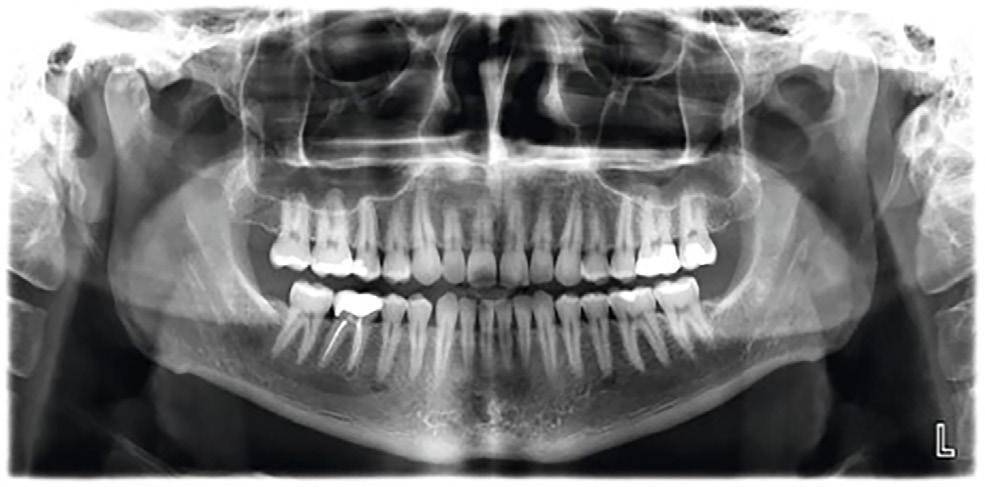

by Larry M. Guzzardo

The process of moving a patient from one member of the team to another is called a “hand-off.” We do this by never leaving a patient alone without letting them know who and what to expect next. It means you never leave them alone in a treatment room, wondering who’ll come in next or how long they will be there, or you never drop them off at the front desk to talk to a receptionist on the phone. It requires informing your patient of each step of the way by explaining who and what comes next, anticipating their needs, and introducing them to the next team member, all while creating an environment that will increase treatment acceptance and reduce canceled and broken appointments.

We all know patients who have been told about a serious dental condition that is getting worse by the minute. And even though we’ve explained the implications of not treating their condition, many patients have still not taken action. It’s because they are unable to “connect the dots” to come to their own conclusion and need more help from us.

That’s why I propose that the patient experience multiple hand-offs throughout their visits. Consider how many times this can happen. The patient needs to be handed off by the dentist to his or her dental assistant. The dental assistant then needs to hand-off the patient perfectly to the front office person, who then also needs to clear everything up with the patient again.

This is what should happen to help patients “connect the dots”: The dentist should be communicating with the patient throughout the appointment about what they are doing, why they are doing it, and how things are progressing. At the end of the appointment, as the chair is brought up, the dentist must take command by coming around to the front of the chair, connect with the patient by making eye-to-eye contact, and take the following 10 steps:

1. Outline exactly what treatment the patient received, including the number of teeth restored, the number of surfaces, and the depths and severities of every tooth restored, in lay terms with no jargon.

4. Let the patient know exactly when he or she should be seen next. It is the dentist’s responsibility to create a sense of urgency for the next appointment. When there is no urgency from the dentist, then it is difficult for the person who schedules your appointments to create that urgency too.

5. Clearly explain the implication (what you’re concerned will happen) if the patient does not proceed with the treatment as planned. The patient needs to be informed about the consequences will be by delaying or ignoring the next appointment.